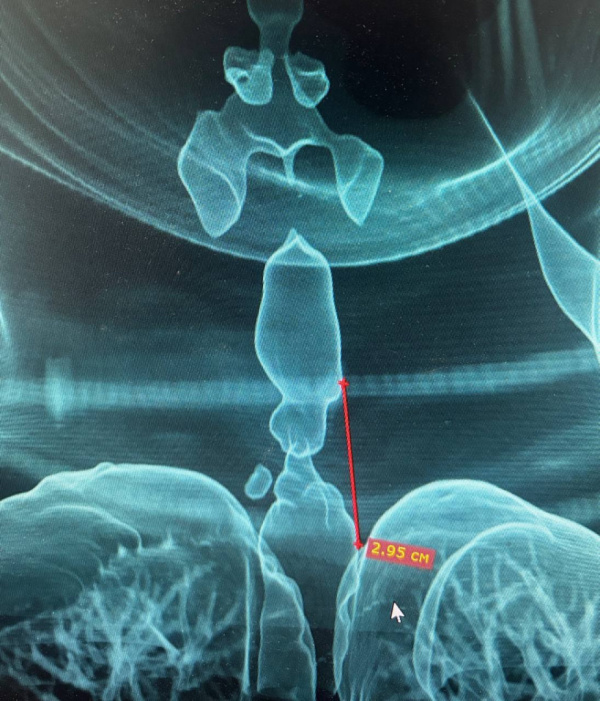

Для постановки диагноза врачи провели бронхоскопию и компьютерную томографию шеи и грудной клетки. Обследование выявило рубцовое сужение трахеи — стеноз. Чтобы точно оценить масштабы проблемы, медики создали трёхмерную модель дыхательных путей пациентки.

Протяжённость суженного участка составила 2,95 см, а минимальный диаметр трахеи сократился до 5 мм. Такое состояние угрожало жизни, поэтому требовалось срочное хирургическое вмешательство. Торакальные хирурги Максим Мясников и Ильяс Гумеров выполнили циркулярную резекцию трахеи, удалив поражённый сегмент и восстановив непрерывность дыхательного пути с формированием межтрахеального анастомоза.